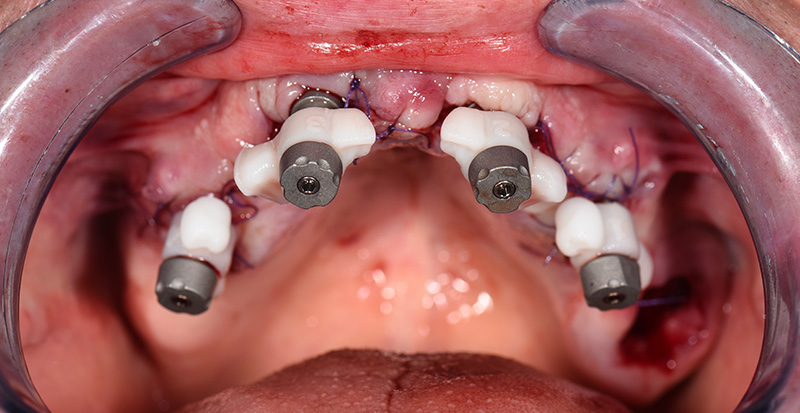

Après le retrait de l’ancien bridge métal-céramique, les dents restantes ont été extraites de manière atraumatique afin de préserver au maximum la paroi vestibulaire de l’os, ce qui est particulièrement important aux emplacements prévus pour la pose des implants. Quatre implants ont été posés immédiatement. Après la mise en place des piliers « multi-unit », une radiographie panoramique de contrôle a été réalisée avant la suture, afin de vérifier la position des implants ainsi que l’adaptation précise des piliers.

Immédiatement après la suture, des piliers de type « Scan-Transfer » de l’entreprise IPD, ont été placés sur les piliers « Multi-unit » (IPD propose des piliers « multi-unit » pour 25 marques d’implants dentaires et 80 plateformes différentes). Ceux-ci permettent une numérisation précise à l’aide d’un scanner intra-oral, selon un protocole spécifique qui évite toute distorsion de l’empreinte dans les zones édentées.

Fig. 05 : Scan-Transfers IPD en place.